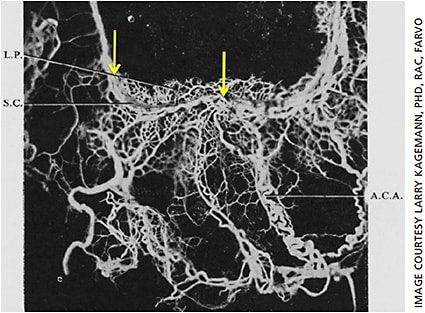

In a series of groundbreaking publications, Norman Henry Ashton, cbe, dsc (Lond), frcp, frcs, gave us our first view of the morphology of the human aqueous humor outflow vasculature.4-6 Best known for his later landmark work demonstrating the role of oxygen in retinopathy of prematurity,7-10 Dr. Ashton’s early research included the creation of physical castings of the aqueous humor outflow pathway. He injected neoprene rubber into Schlemm’s canal (Figure 1) with sufficient pressure to fill the distal vasculature. Surrounding tissue was dissolved with acid, leaving a cast of Schlemm’s canal and the distal vasculature.5 This was the first visualization of the dense vascular network of aqueous humor vessels surrounding Schlemm’s canal.

Focusing on Schlemm’s canal, we can observe in Figure 2 portions of the canal that separate into multiple parallel passages (yellow arrows) which then come back together into a single channel.5 These observations of local splitting and convergence of the canal challenge the dogma of a single intrascleral passage, which remains pervasive to this day. Also note that the presentation of Schlemm’s canal in Figure 2 is that of a large passageway. High pressure was needed to push the viscous neoprene through the canal and into the distal vasculature. It is possible that the pressure required to make these castings distended the canal to nonphysiological proportions.